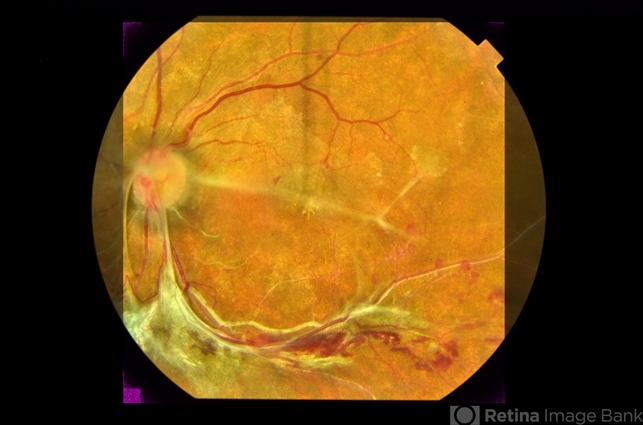

- fundus photograph, fibrovascular proliferation

- Fundus photograph of an 58-year-old female patient with fibrovascular proliferation product of an occlusion of ancient venous branch.